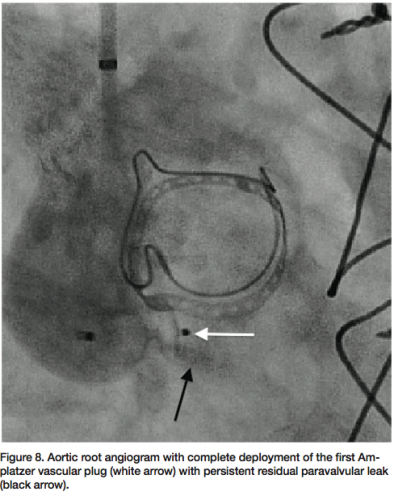

The patient underwent general anesthesia and endotracheal intubation for TEE evaluation in the cardiac catheterization laboratory. The paravalvular leak was crossed using a 6 French multipurpose diagnostic catheter and angled Glidewire, followed by a 6 French shuttle sheath (Cook Medical) over an Amplatz stiff wire (Figure 7). Using TEE and fluoroscopy, an 8 mm Amplatzer vascular plug II (AGA Medical) was deployed successfully, with persistent moderate regurgitation from the anteromedial region of the paravalvular aortic leak (Figure 8). The defect was

recrossed with a 5 French EBU guide catheter (Medtronic), followed by placement of a second 8 mm Amplatzer vascular plug (Figure 9). Final angiography (Figure 10) and TEE (Figure 11) of the paravalvular leak after two adjacent vascular plugs demonstrated no significant residual paravalvular leak. All catheters and sheaths were removed, with hemostasis achieved using a vascular closure device. The patient was discharged home without complications the following day.